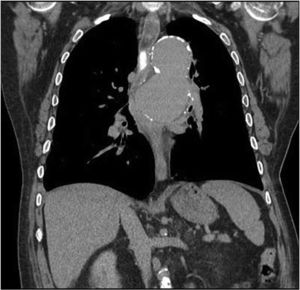

Sixty-four-year-old male with a history of thoracic aortic aneurysm who came to the emergency department due to the feeling of blockage at mid-oesophageal level which led to vomiting after eating. He denied bolus obstruction. He reported the presence of strands of blood in the most recent vomiting, as well as dyspnoea and orthopnoea. A chest X-ray showed an increase in the size of the aortic aneurysm, which led to a CT-angiogram being performed, showing hyperdense content in the oesophageal lumen, as well as signs of instability and penetrating ulcer which was in contact with and compressed the oesophageal lumen and the left bronchus (Figs. 1 and 2). Urgent surgery was performed with the fitting of an aortic stent, with no immediate complications. At 48h, the patients presented with haematemesis, with gastroscopy showing a mid-oesophageal clot and pulsating bleeding. In view of a suspected endoleak a surgical review was performed, with the arteriography showing no periprosthetic leakage. The patient presented with haemodynamic shock which did not respond to multiple transfusions or vasoactive drugs, leading to death. In the autopsy, the presence of an aortoesophageal fistula was confirmed (Fig. 3).

Oesophageal dysphagia secondary to extrinsic vascular compression is a rare cause of dysphagia, with the presence of cardiovascular abnormalities being the most common cause.1 Aortic dysphagia refers to dysphagia brought about by atherosclerosis or aortic aneurysm.2 Clinical manifestations of dysphagia and upper gastrointestinal haemorrhage may appear in complicated aneurysms, as in the case of our patient, with secondary aortoesophageal fistula being a complication with high mortality.3